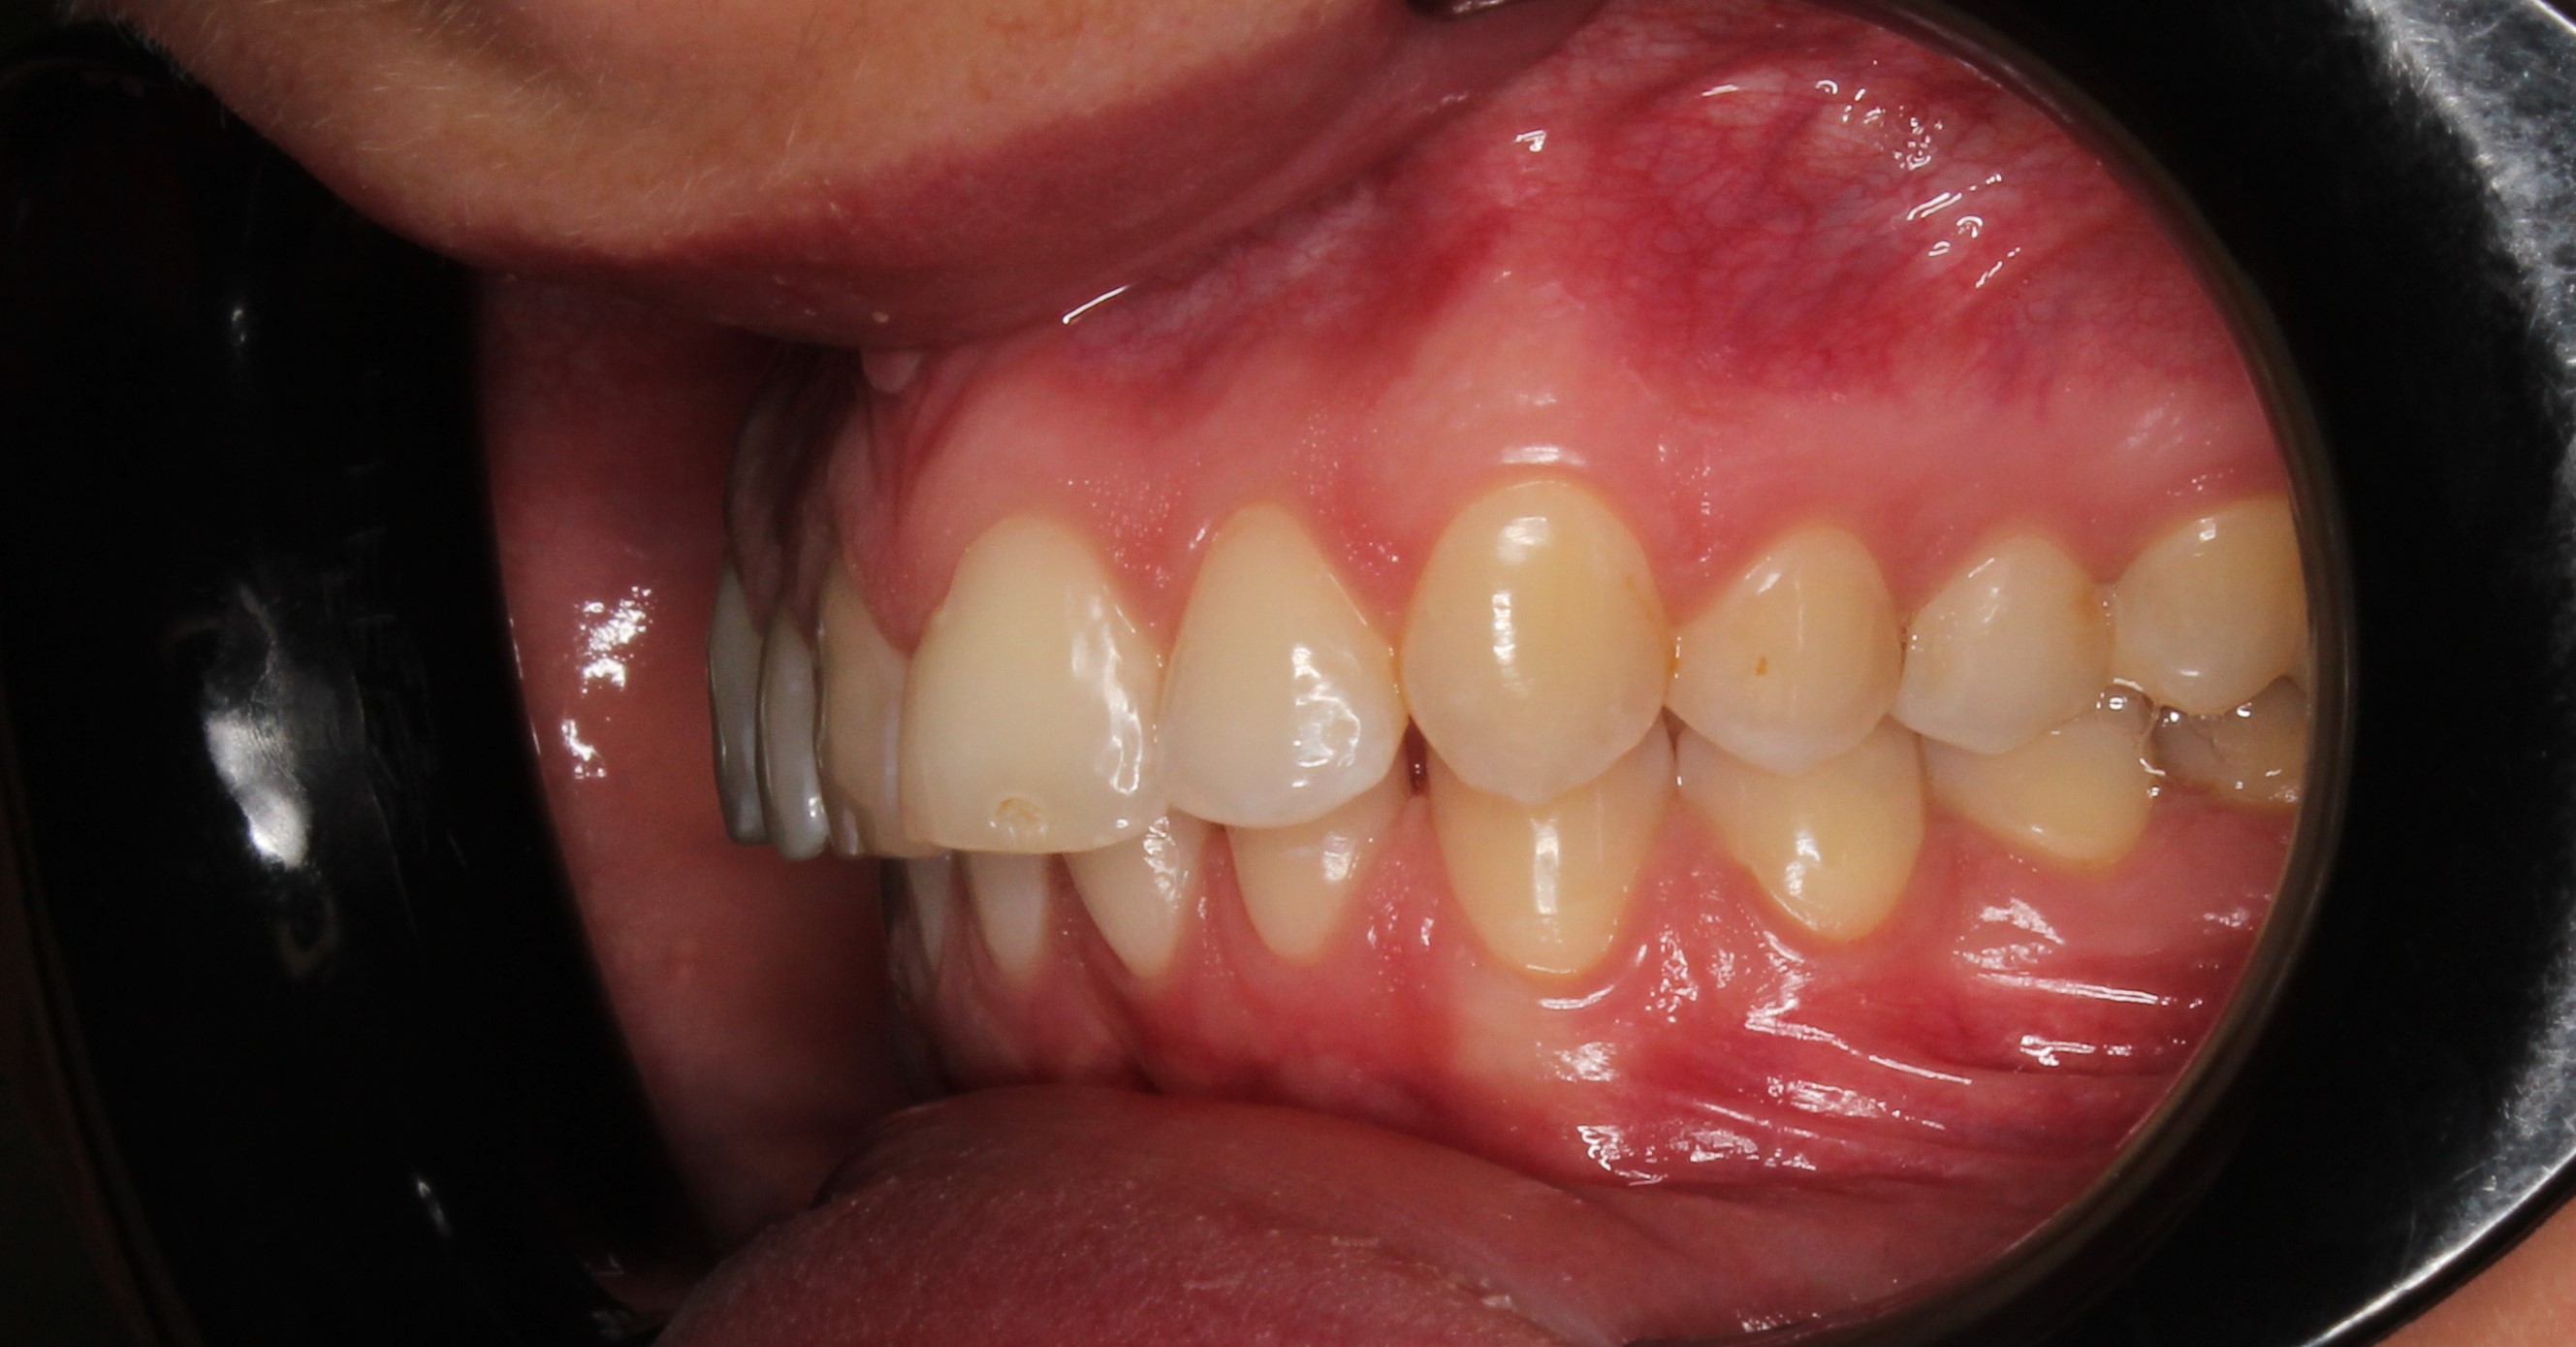

До и После: Лечение глубокого прикуса с помощью элайнеров Eurokappa